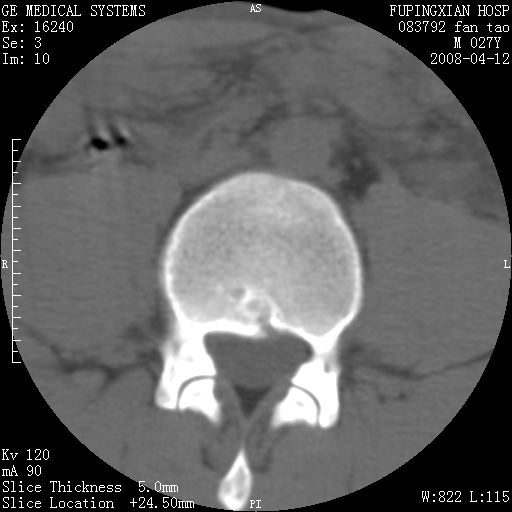

以下是引用前行在2008-4-13 13:53:00的发言:[br]椎间盘髓核终板下突出形成许莫氏结节及椎间盘突出,建议mr检查

以下是引用xclzq_910在2008-4-13 12:43:00的发言:[br]这个应该没什么了,椎间盘突出后反应性骨质吸收硬化.建议mr